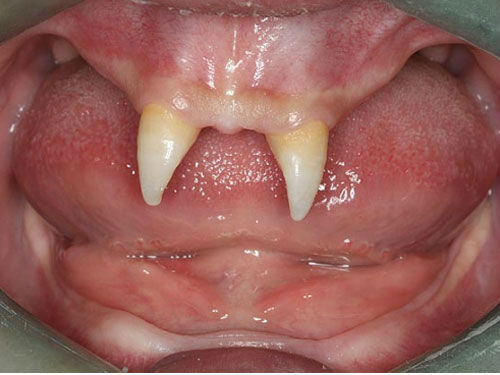

(18:04:43 PM 22/12/2012)Wang Pengfei, 16 tuổi, sống tại thành phố Trùng Khánh, Tây Nam Trung Quốc. Sinh ra đã mắc phải một chứng bệnh lạ, Pengfei có rất ít tóc và chỉ mọc duy nhất 2 chiếc răng nhọn hoắt.

| Cậu bé Trung Quốc có hàm răng phát triển lạ kỳ. |

Bà Wang Hui - mẹ của Pengfei đã đưa cậu đến bệnh viện địa phương để kiểm tra y tế hồi đầu tuần. Bà Wang cũng đã nhiều lần đưa con đi khám với mong muốn sẽ có cách chữa trị hàm răng cho con trai nhưng đều không nhận được kết quả khả quan.

Theo các bác sĩ ở bệnh viện Tây Nam, Pengfei chỉ có thể phẫu thuật khi ở tuổi trưởng thành. Chi phí cho ca phẫu thuật này là khoảng 70.000 đến 80.000 nhân dân tệ (tương đương 235 đến 270 triệu đồng).